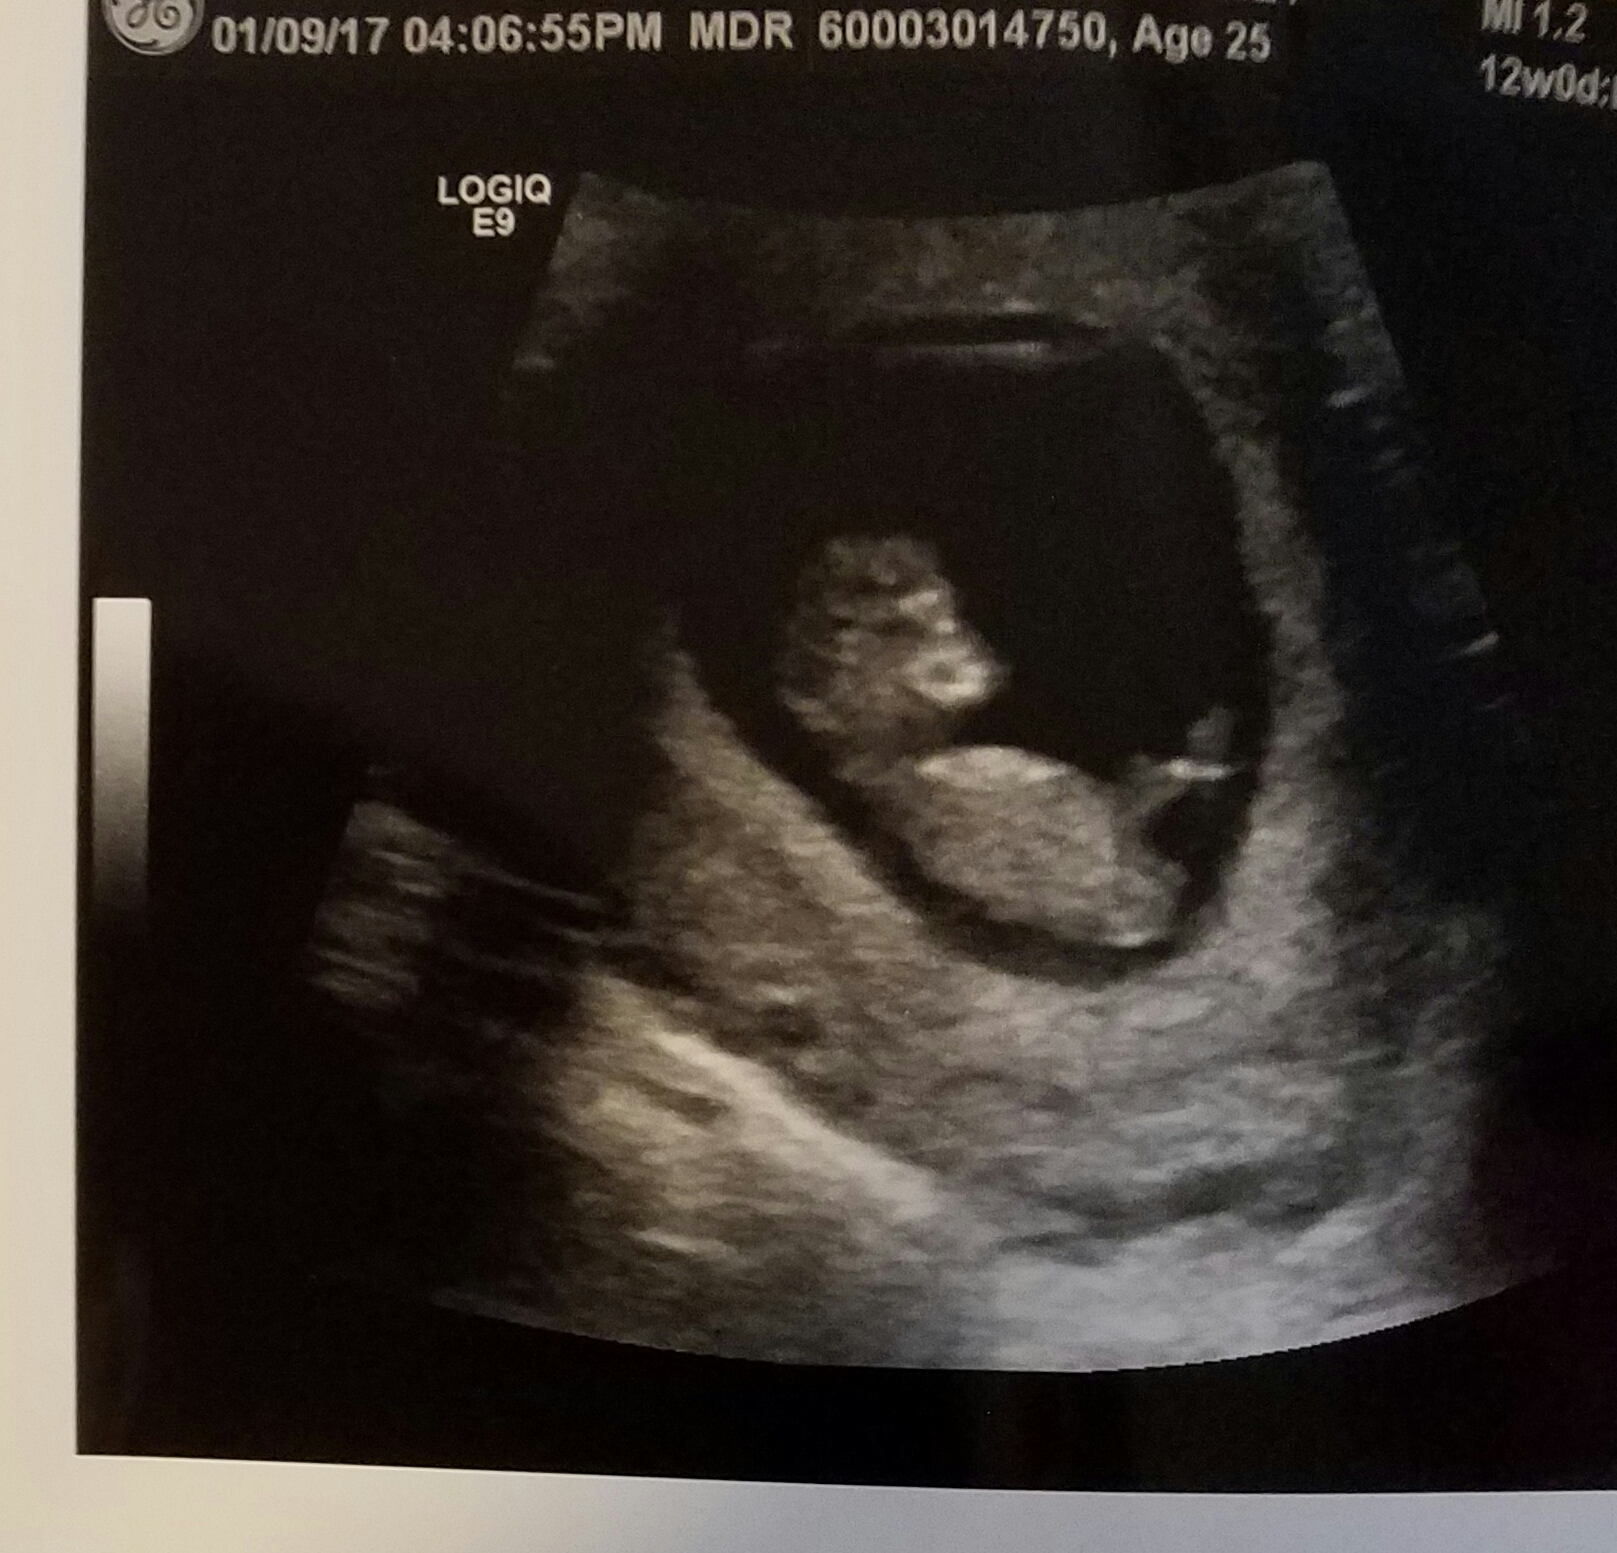

Would love to hear guess on gender!!

Maybe boy?